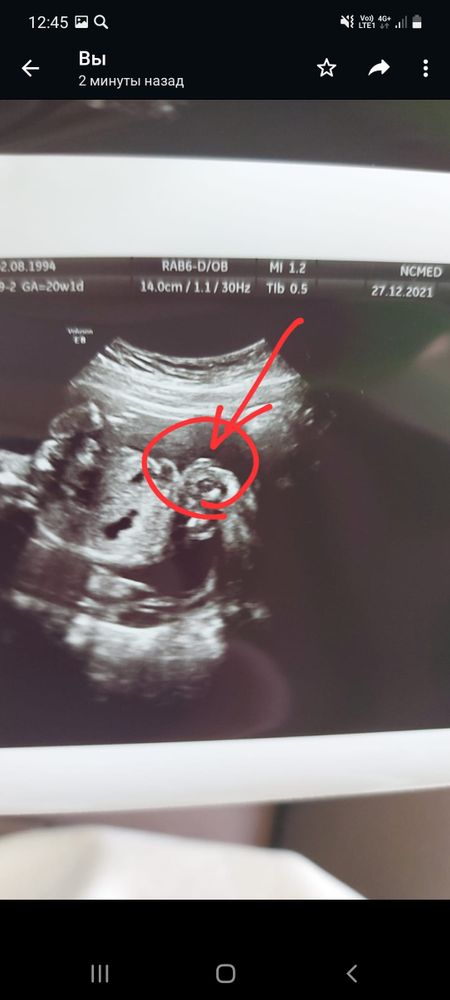

Кто на узи ,20 нед?

Я вижу вообще зайца в профиль🤗♥️ Изображение

Еле разобралась где что, мальчик.

Елена, как ни странно, но врач сказала что девочка) вид далеко не снизу,а скорее всего бок. Родственники недоумевают ,что там за бугор у девочки в 20.1 нед 😃😃

Как по мне это мальчик)))

Это вид снизу? Сбоку?

Karmilla, самой не очень понятно.наверно бок ,спина. Но не вид снизу 🤷‍♀️

Тут уже и видно хорошо. Что мальчик

Dasha, все родственники,знакомые тоже видят мальчика) врач сказала что девочка. Все просто не поймут, что там за бугор у девочки в 20.1нед😃